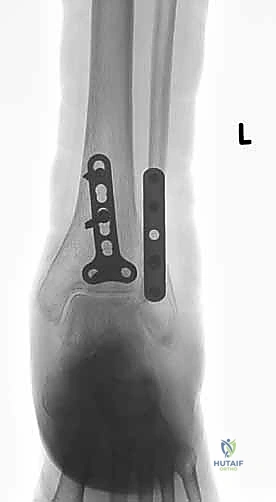

المرحلة الثالثة: رد العظام وتثبيت الكعب الوحشي (الشظية)

يبدأ الجراح عادة بإصلاح الشظية لأنها تعتبر "العمود الفقري" لاستقرار الكاحل. يتم إرجاع قطع العظم إلى مكانها التشريحي الطبيعي (الرد المفتوح). ثم يتم تثبيتها باستخدام شريحة معدنية (Plate) ومجموعة من المسامير (Screws) لتثبيتها بقوة.

المرحلة الرابعة: تثبيت الكعب الإنسي (الظنبوب)

بعد استقرار الجانب الخارجي، ينتقل الجراح للجانب الداخلي. يتم تنظيف منطقة الكسر من أي أنسجة محشورة، ثم يتم رد الكعب الإنسي وتثبيته غالباً باستخدام مسمارين طويلين (Cancellous screws) أو تقنية الأسلاك والشد (Tension band wiring) حسب شكل الكسر.